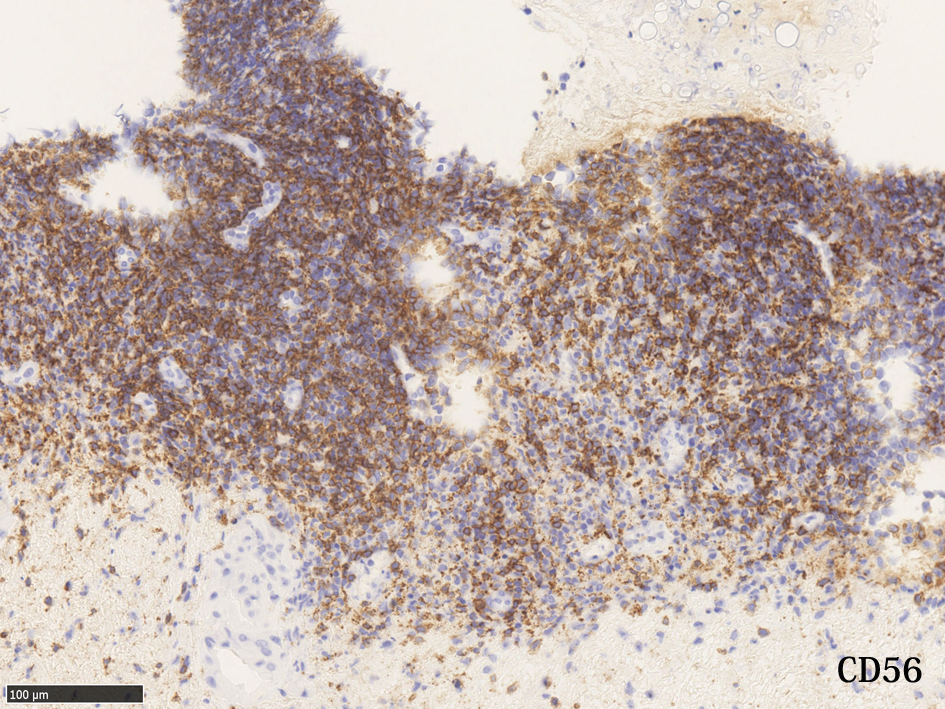

extranodal natural killer/ T-cell lymphoma, nasal type

鼻, 副鼻腔領域より採取された組織が, 壊死の強い炎症性肉芽組織の場合, 浸潤細胞にリンパ球が含まれていれば絶対CD56は染めておくようにしたい

鼻・副鼻腔の壊死組織では extranodal natural killer/T-cell lymphoma, nasal typeを見落とさないことが大事 浸潤しているリンパ球は小型リンパ球で異型の見られないことが多い.

IWT case 64year-old female

左から鼻腔より採取された壊死組織断片。真菌の増殖がある。よく見ると腺周囲に小型の異型所見に乏しいリンパ球が密に浸潤している。念のためCD56を染めると多くのリンパ球が陽性を示しNK/T-cellの浸潤増殖の可能性がでてきた。EBER-ISHではB細胞に陽性となっている所見。以上からNK/T-cell lymphoma nasal typeの壊死病変を採取したことが強く疑われ臨床科に連絡して精査, 再度確定診断をおこなうようになった。

3.小型低異型度型--->組織像図3 小型で低異型度のリンパ球がびまん性に浸潤. 慢性炎症との鑑別が難しい. 上記の症例.

診断はCD3+(細胞質+, 表面-; FCMの抗体ではsCD3は陰性となる), CD56+, CD5-, cytotoxic molecule[granzymeB, TIA-1, perforin,etc]を染色, EBER-ISHでEBVの存在を確認する.